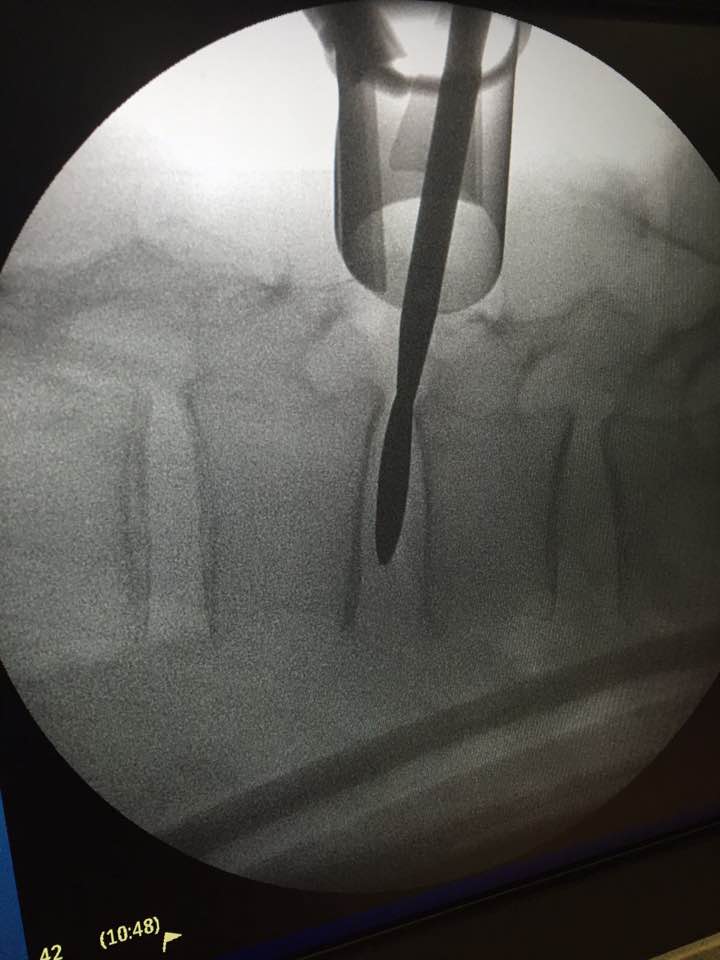

Lumbar intervertebral foramina epidural nerve root injection

After injecting spinal nerve roots with anesthesia, confirming the cause of spinal sciatica symptoms. I can tell the patient whether lumbar screw fusion is helpful.